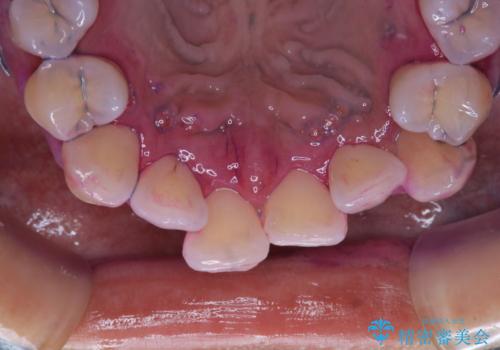

矯正治療が始まる前に歯磨きチェックとクリーニング

- 矯正治療がまもなくスタートするため、きれいにしたいのと歯磨きを上達したいとのことでした。染め出しをしての歯磨きチェック・指導とPMTC30分コースを行いました。

染め出し液を使ってプラークを染め出すことにより、普段の歯みがきで磨き残している場所を目で確かめることができます。

日々の歯磨きを上達するには、まずどこが磨けていないか認識することが大切です。